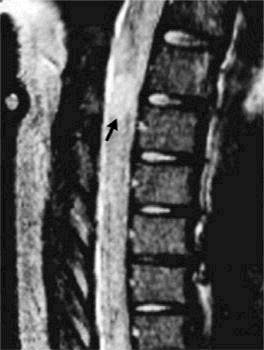

| Mielitis:

en pacientes inmunocompetentes, la infección por VVZ puede complicarse

con el desarrollo de una mielitis, generalmente se desarrolla entre 1 y

2semanas

después del rash cutáneo. Clínicamente se caracteriza

por paraparesis sensitiva y alteración de la función de los

esfínteres, que en la mayoría de los pacientes mejora de

forma progresiva. Enpacientes

inmunodeprimidos la mielopatia es por lo general insidiosa y progresiva

(Figura 3)

Figura 3. Imagen de resonancia magnética de la médula espinal mostrando una mielitis producida por la infección por el virus de varicela-zoster en un paciente inmunocompentente. El paciente desarrollo una paraplejia poco después del inicio de un zoster. La lesión se observa en la médula a nivel toracico con la uitilización de gadolinium |